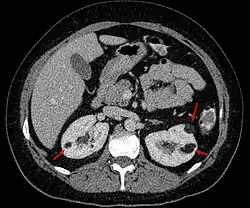

- In der Computertomographie zeigt sich eine durch den hohen Fettgehalt bedingte hypodense Raumforderung in der Niere mit −20 bis −80 Hounsfield-Einheiten. Dies ermöglicht eine Abgrenzung zum Nierenzellkarzinom. Bei den Angiomyolipomen kommen Verkalkungen nicht vor.